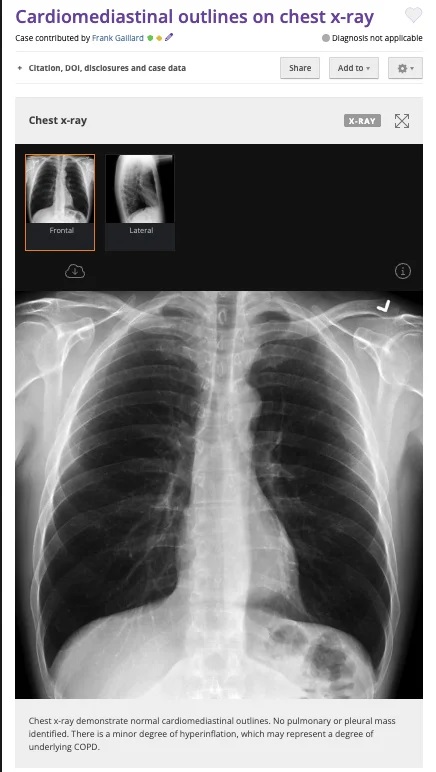

Orijinal görüntü 22 Ocak 2010’da bir radyoloji görüntüleri deposu olan “Radiopedia” üzerinden yayınlanmış.